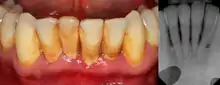

Photograph (left) and a radiograph (right) demonstrating extensive bone loss and soft tissue inflammation due to periodontitis. Plaque, calculus and staining

The defining feature of periodontitis is connective tissue attachment loss which may manifest as deepening of periodontal pockets, gingival recession, or both. This loss of support for the teeth is essentially irreversible damage. Chronic periodontitis is generally slow to moderate in terms of disease progression, although short bursts of increased tissue destruction may occur. Ultimately, tooth loss may occur if the condition is not halted. It is termed localized when less than 30% of sites around teeth are involved, and generalised when more than 30% are involved. clinical attachment loss can be used to determine the severity of the condition, where 1–2mm is slight, 3–4mm is moderate and more than 5mm is severe.[5]